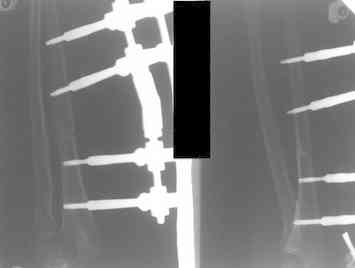

Артротомия, иссечение рубцов, остатков кольцевидной связки. На проксимальный отдел локтевой кости стержневой аппарат (рекомендуют

Compact II выпущеный Stryker Howmedica, но за неименеем...), остеотомия проксимального отдела локтевой кости, вправление головки лучевой кости, замыкание аппарата, проверка стабильности головки

У нас были проблемы. Скорее всего связанные с использованием стержневого аппарата с простым соединением. В Компакте же скорее всего шарнирное, со свободой движения во всех плоскостях, что конечно, значительно должно упрощать фиксацию в правильном положении.